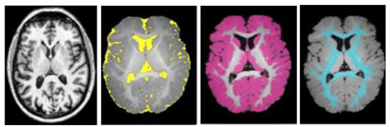

2.2. Segmentation of Brain Regions

2.2.1. Related-Work to the Segmentation of Brain Regions